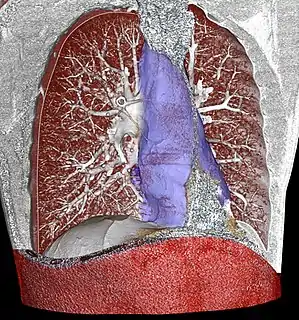

![]() Mediastinum. The division between superior and inferior is at the sternal angle. | |

The mediastinum can be divided into an upper (or superior) and lower (or inferior) part:

- The superior mediastinum starts at the superior thoracic aperture and ends at the thoracic plane.

- The inferior mediastinum from this level to the diaphragm. This lower part is subdivided into three regions, all relative to the pericardium – the anterior mediastinum being in front of the pericardium, the middle mediastinum contains the pericardium and its contents, and the posterior mediastinum being behind the pericardium.[6]

Thoracic plane

The transverse thoracic plane, thoracic plane, plane of Louis or plane of Ludwig is an important anatomical plane at the level of the sternal angle and the T4/T5 intervertebral disc.[8][9][10] It serves as an imaginary boundary that separates the superior and inferior mediastinum. [8][9][10]